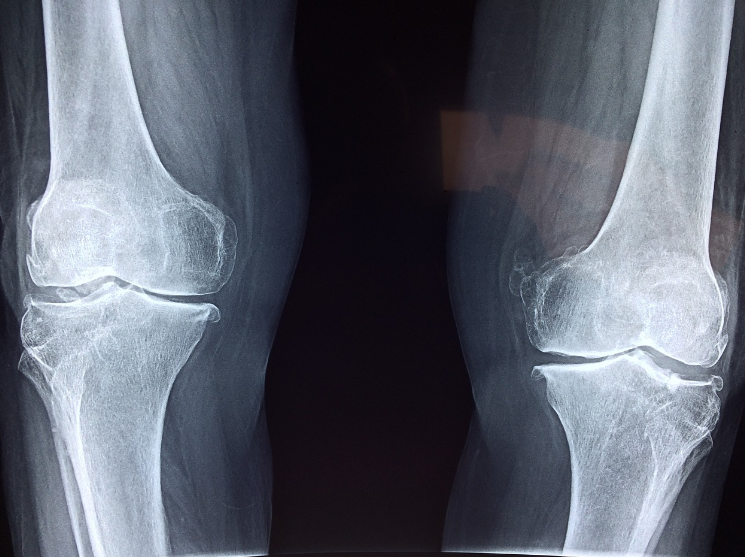

'골다공증'이란 뼈의 밀도와 질량이 감소함으로써, 뼈가 약해지고 쉽게 부러질 위험성이 증가하는 질환입니다.

골다공증은 보통 '침묵의 질병'이라 불리고 있는데, 이는 초기에 뚜렷한 증상이 나타나지 않는 경우가 많기 때문입니다.

가벼운 충격을 받거나 살짝 넘어진 경우에도 뼈가 쉽게 부러질 수 있으며, 특히 손목과 척추, 고관절 부위에서 골절이 자주 발생합니다.

척추 압박 골절

척추뼈가 점차 약해짐으로 인해 압박 골절이 발생하면, 등이 굽거나 키가 줄어드는 현상이 나타납니다.